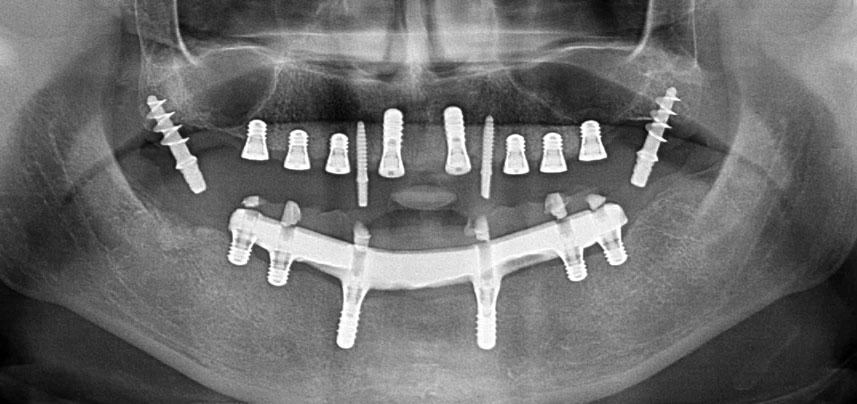

Eine 41-jährige Patientin ohne systemische Besonderheiten hatte aufgrund von Parodontitis und Karies alle Zähne verloren. Zuletzt musste sie im Ober- und Unterkiefer schleimhautgetragene Totalprothesen tragen, was wegen deren schlechter Passung große Probleme beim Kauen verursachte. Die Patientin entschied sich, Implantate für eine steggetragene CAD/CAM-Prothese im Unterkiefer setzen zu lassen.

Drei Jahre später war es Zeit für eine gleichartige Oberkieferprothese. Basierend auf der DVT-Planung wurde durch Verwendung kurzer Implantate eine Sinusaugmentation vermieden und die geplanten Implantatpositionen wurden mit einer Bohrschablone auf den Kieferkamm übertragen (Abb. 1 und 2).

Wegen des relativ harten Knochens (D2) an den Positionen 11 und 21 wurden die 10 mm langen Implantatlager in diesem Bereich abschließend mit einem 4-mm-Spiralbohrer, dem chirurgischen Winkelstück WS-75 L von W&H und dem W&H Implantmed Implantologiemotor in Verbindung mit dem optionalen W&H Osstell ISQ module präpariert. Im Gegensatz dazu wurde der weiche Knochen der Implantatlager im Seitenzahnbereich mit dem Piezomed I3P auf den abschließenden Durchmesser von 3 mm erweitert. Die Implantate wurden dann transgingival eingesetzt, die Einheildauer betrug drei Monate (Abb. 6-10). Die vorhandene Prothese wurde auf vier provisorischen Implantaten abgestützt (Abb. 8).